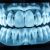

Nie bój się wizyt u stomatologa! Dobry dentysta i ortodonta w Warszawie

Aby móc cieszyć się w pełni zdrowym i pięknym uśmiechem trzeba niekiedy zdecydować się na dość radykalne kroki. Takim działaniem z pewnością jest usunięcie zębów – niestety, w niektórych przypadkach nie da się już podjąć skutecznego leczenia, przez co jest to jedyne wyjście. W takich sytuacjach konieczne może być szybkie uzupełnienie wszystkich ubytków w jamie ustnej. Pozbawione elementu swojej struktury pozostałe zęby mogą zmieniać...

Protezy zębowe – szeroki wybór: korony porcelanowe, protezy nylonowe

Różnego rodzaju ubytki w uzębieniu mogą niestety przytrafić się każdemu z nas. Istnieje bardzo wiele przyczyn, dla których takie problemy w ogóle się pojawiają. Niekiedy tracimy zęby przez nasze własne zaniedbania. Nieprawidłowa dieta i brak należytej higieny jamy ustnej mogą spowodować, że nasze zęby staną się bardzo zniszczone i jedynym rozwiązaniem będzie ich usunięcie. Niekiedy przyczyną jest wiek – wraz z upływem czasu...